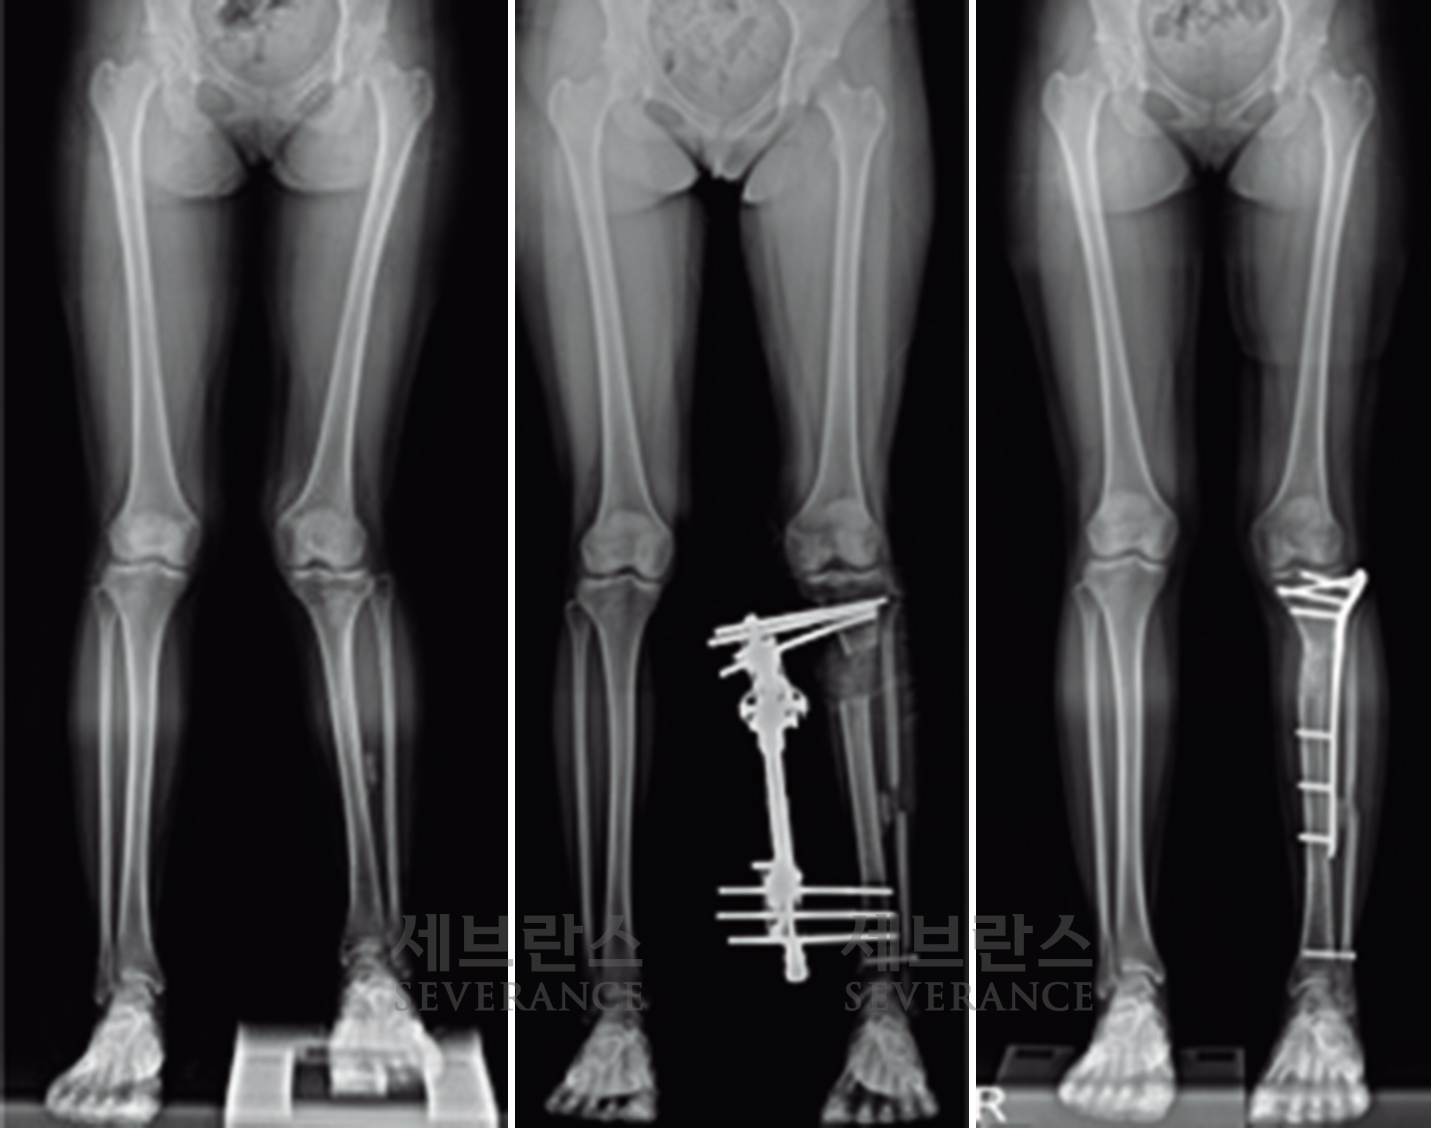

성장이 끝난 환자나 변형이 심한 경우에는 절골 교정술이 효과적입니다. 이 수술은 뼈를 잘라 바른 위치로 되돌린 뒤 금속 장치로 고정하는 방식으로, 수술 직후 곧바로 교정 효과를 볼 수 있습니다. 그러나 절골된 뼈가 단단히 붙을 때까지 약 2-3개월이 소요되며, 그동안은 목발 보행 등 활동에 제약이 따릅니다.

양쪽 팔다리의 길이 차이가 큰 경우에 주로 시행하는 수술로, 외부 고정 장치나 내부 금속정을 이용해 뼈를 서서히 늘려 균형을 맞추는 방법입니다. 대체로 외부 고정 장치를 많이 사용하는데, 연장 기간 동안 날마다 정해진 횟수만큼 뼈를 조금씩 늘려야 하고, 핀 주변 소독도 꾸준히 해줘야 합니다. 연장된 뼈가 단단히 붙는 데도 수개월이 걸리기 때문에 환자와 보호자의 인내가 필요합니다.

특발성 대사성 질환으로 인한 외반슬(X다리)에서 성장조절술을 시행한 환아성장판

구루병으로 발생한병적 내반슬(O다리) 변형에 대해

절골 교정술을 시행한 환아

성장판 손상으로 발생한 좌측 외반슬 및 하지부동에 대해 골연장술과 교정술을 동시에 시행해 치료한 환아